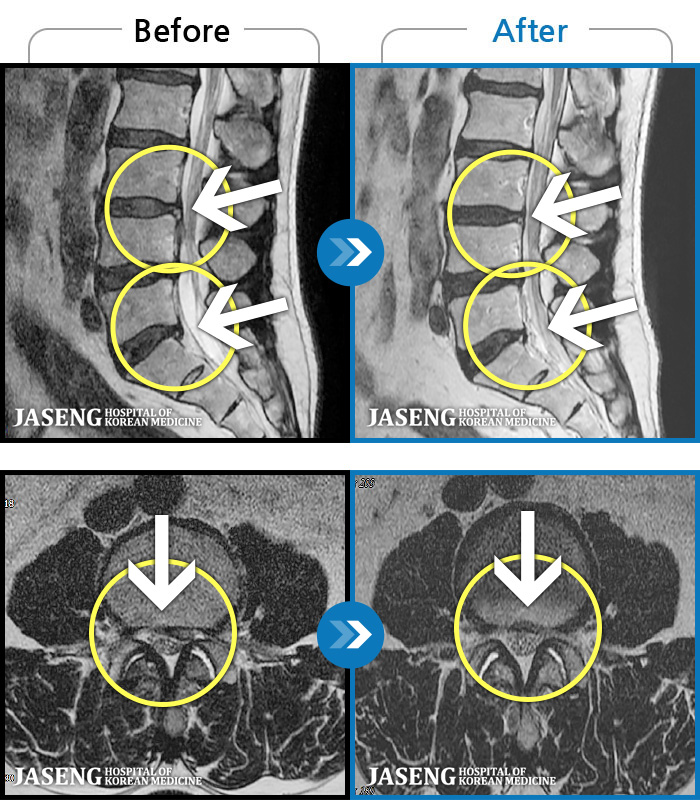

MRI ġ

1,243 MRI ũ ʸ Ȯϼ.